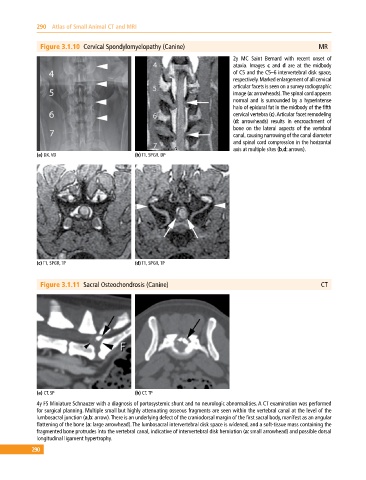

Figure 3.1.10 Cervical Spondylomyelopathy (Canine) MR

2y MC Saint Bernard with recent onset of

ataxia. Images c and d are at the midbody

of C5 and the C5–6 intervertebral disk space,

respectively. Marked enlargement of all cervical

articular facets is seen on a survey radiographic

image (a: arrowheads). The spinal cord appears

normal and is surrounded by a hyperintense

halo of epidural fat in the midbody of the fifth

cervical vertebra (c). Articular facet remodeling

(d: arrowheads) results in encroachment of

bone on the lateral aspects of the vertebral

canal, causing narrowing of the canal diameter

and spinal cord compression in the horizontal

axis at multiple sites (b,d: arrows).

(a) DX, VD (b) T1, SPGR, DP

(c) T1, SPGR, TP (d) T1, SPGR, TP

Figure 3.1.11 Sacral Osteochondrosis (Canine) CT

(a) CT, SP (b) CT, TP

4y FS Miniature Schnauzer with a diagnosis of portosystemic shunt and no neurologic abnormalities. A CT examination was performed

for surgical planning. Multiple small but highly attenuating osseous fragments are seen within the vertebral canal at the level of the

lumbosacral junction (a,b: arrow). There is an underlying defect of the craniodorsal margin of the first sacral body, manifest as an angular

flattening of the bone (a: large arrowhead). The lumbosacral intervertebral disk space is widened, and a soft‐tissue mass containing the

fragmented bone protrudes into the vertebral canal, indicative of intervertebral disk herniation (a: small arrowhead) and possible dorsal

longitudinal ligament hypertrophy.